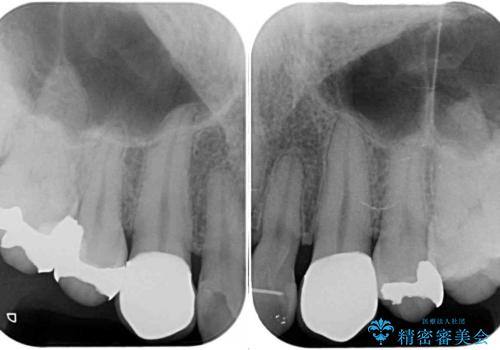

- 以前矯正を行った際に前歯が虫歯だらけとなり、審美面を気にして来院された患者様です。

虫歯の大きかった左右犬歯はオールセラミッククラウンで補綴治療をおこない、4前歯は研磨や古い充填物の詰め直しを行いました。